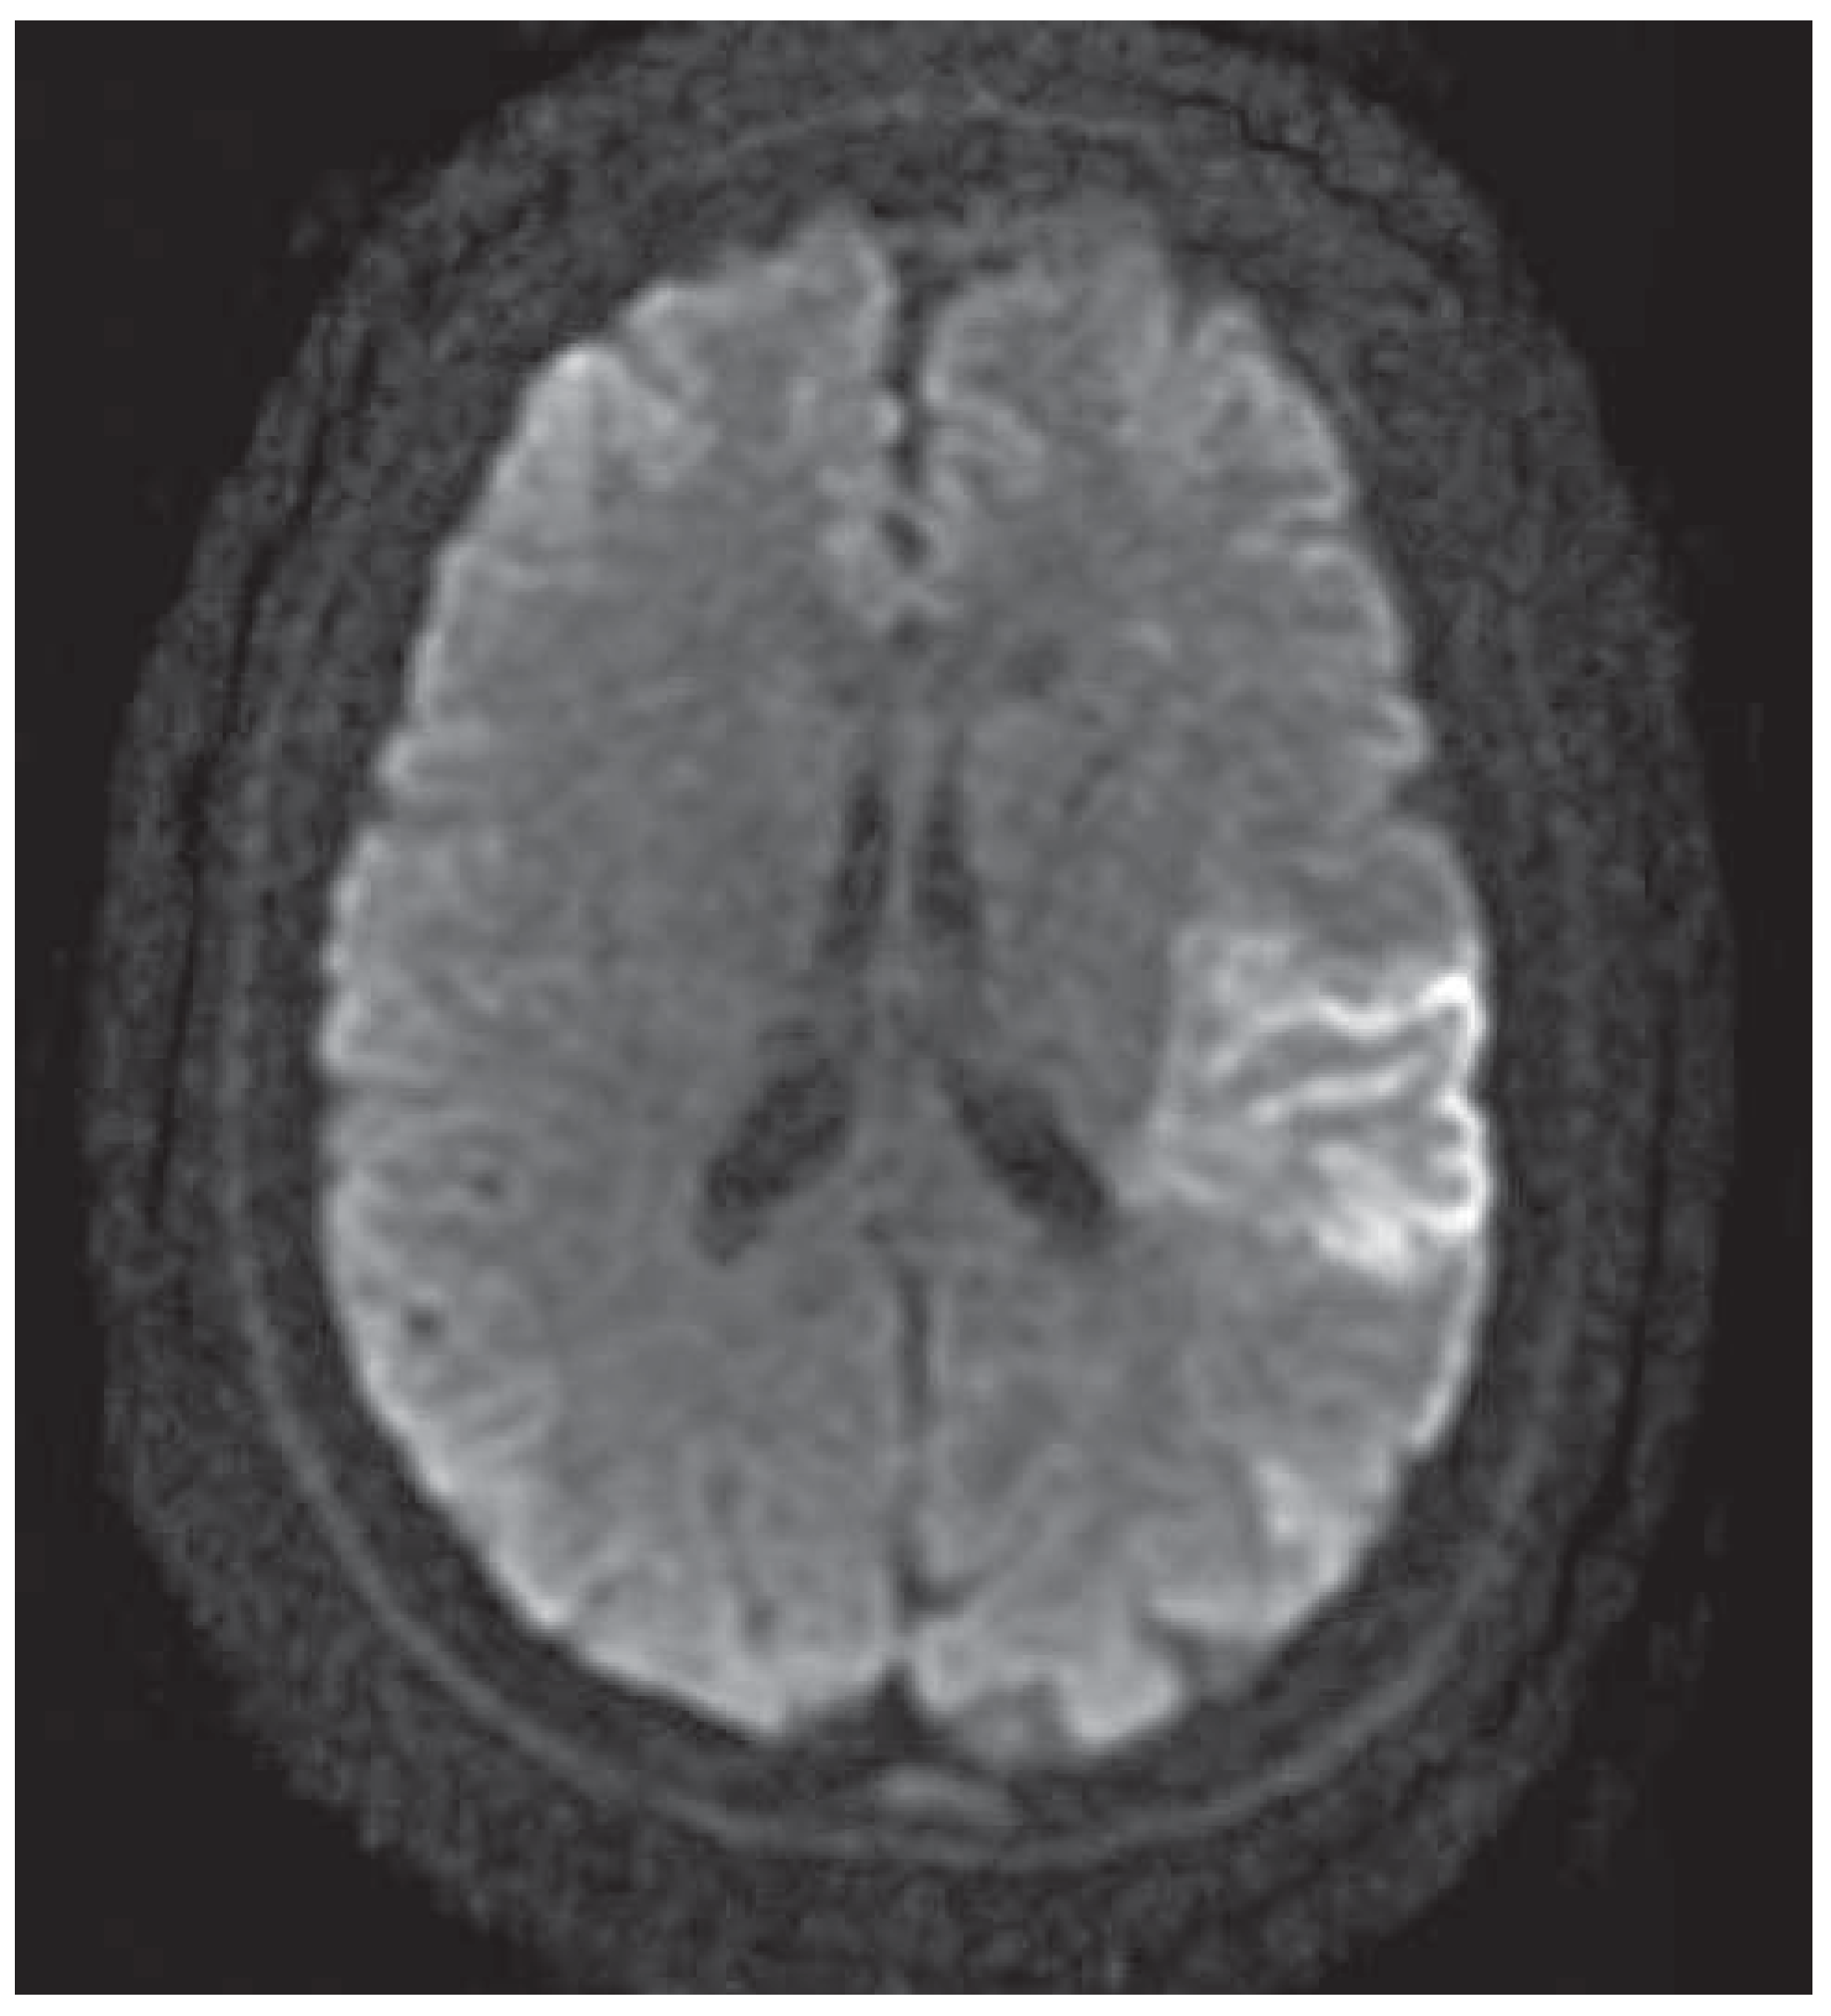

Mechanical Thrombectomy After Embolic Internal Carotid Artery Occlusion in Acute Stroke

Case presentation